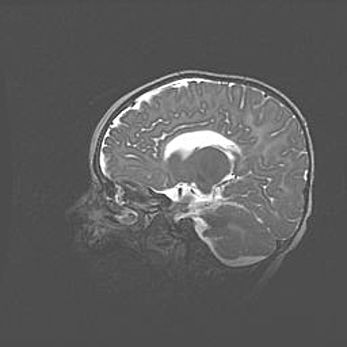

Подострая гематома правой гемисферы мозжечка.

Наружная гидроцефалия.

Возраст: 15 дней

Вес: 3100 г

Пол: женский

Окружность головы: 37 см

Срок гестации: 35-36 недель

При открытой наружной форме гидроцефалии у новорожденных расширяются и переполняются субарахноидные пространства.

Кровоизлияния в мозжечок имеют две клинико-анатомические формы: полушарные гематомы и кровоизлияния в червь.

К появлению этой патологии может привести: повреждения головного мозга, возникающие в результате асфиксии и гипоксии плода при беременности, или травмы во время родов. Редко гематома мозжечка может быть результатом первичной коагулопатии и сосудистой мальформации, диссеминированном внутрисосудистом свертывании, изоиммунной тромбоцитопении.